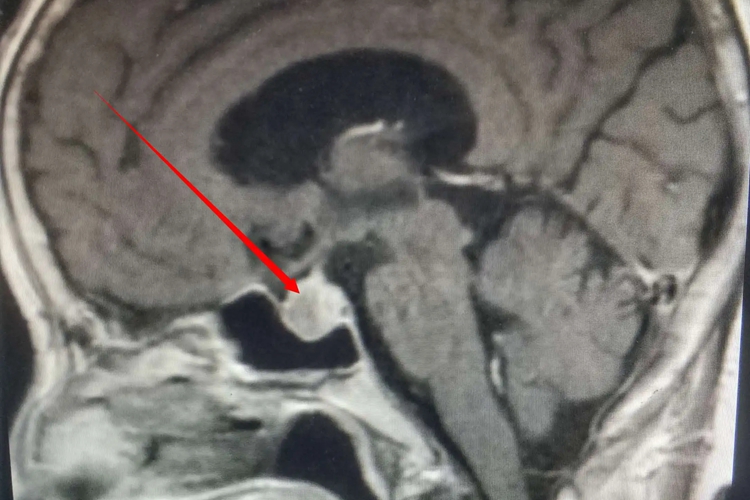

脑垂体MRI图像即为脑部脑垂体的磁共振成像,脑垂体位于颅骨的蝶鞍垂体窝内,为一椭圆形小体,由腺垂体和神经垂体两部分组成。脑垂体的腺垂体(垂体前叶)呈等T1和等T2信号,位于鞍内前3/4区;神经垂体(垂体后叶)呈短T1和等T2信号,占据垂体窝后部1/4区。

头部鞍区的骨性结构在MRI上呈低信号,不如CT清楚,但显示软组织结构明显优于CT,故脑垂体行MRI检查较CT清楚。MRI检查是通过图像上反映T1值和T2值的黑白灰度及其改变,来检出病变并进行诊断的,根据脑垂体的信号显示结果可判断是否存在相关疾病。